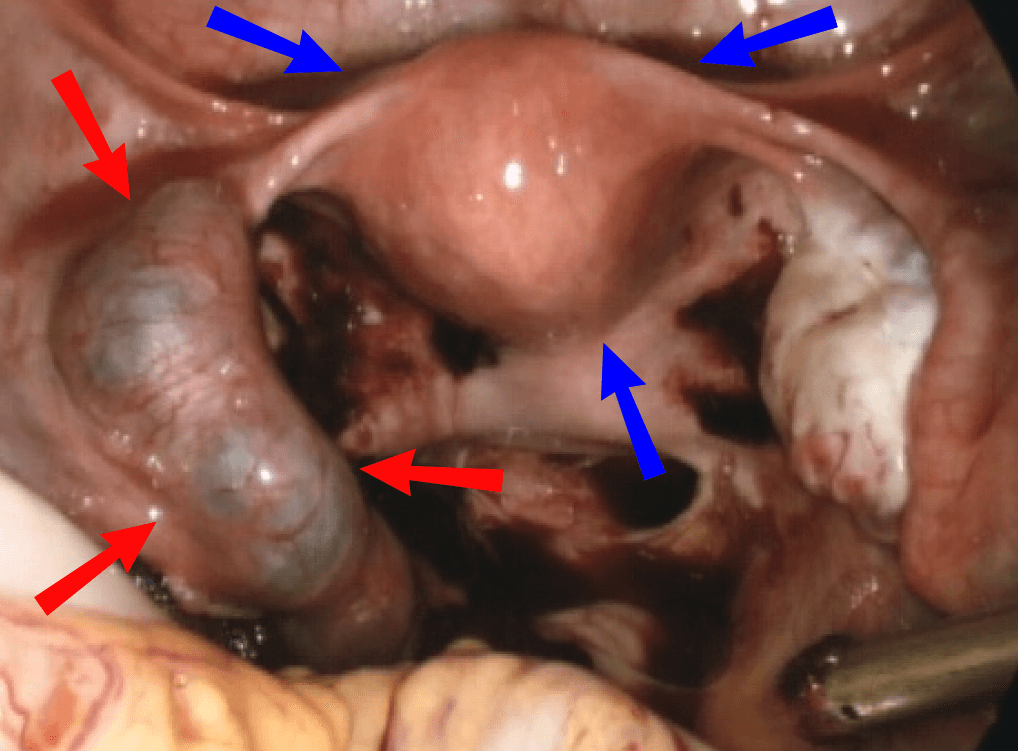

Ectopic pregnancy is a complication of pregnancy in which the embryo attaches outside the uterus. Signs and symptoms classically include abdominal pain and vaginal bleeding, but fewer than 50 percent of affected women have both of these symptoms. The pain may be described as sharp, dull, or crampy. Pain may also spread to the shoulder if bleeding into the abdomen has occurred. Severe bleeding may result in a fast heart rate, fainting, or shock. With very rare exceptions, the fetus is unable to survive. Overall, ectopic pregnancies annually affect less than 2% of pregnancies worldwide. Risk factors for ectopic pregnancy include pelvic inflammatory disease, often due to chlamydia infection; tobacco smoking; prior tubal surgery; a history of infertility; and the use of assisted reproductive technology. Those who have previously had an ectopic pregnancy are at much higher risk of having another one. Most ectopic pregnancies (90%) occur in the fallopian tube, which are known as tubal pregnancies, but implantation can also occur on the cervix, ovaries, caesarean scar, or within the abdomen. Detection of ectopic pregnancy is typically by blood tests for human chorionic gonadotropin (hCG) and ultrasound. This may require testing on more than one occasion. Other causes of similar symptoms include: miscarriage, ovarian torsion, and acute appendicitis. Prevention is by decreasing risk factors such as chlamydia infections through screening and treatment. While some ectopic pregnancies will miscarry without treatment, the standard treatment for ectopic pregnancy is a procedure to either remove the embryo from the fallopian tube or to remove the fallopian tube all together. The use of the medication methotrexate works as well as surgery in some cases. Specifically it works well when the beta-HCG is low and the size of the ectopic is small. Surgery such as a salpingectomy is still typically recommended if the tube has ruptured, there is a fetal heartbeat, or the woman's vital signs are unstable.